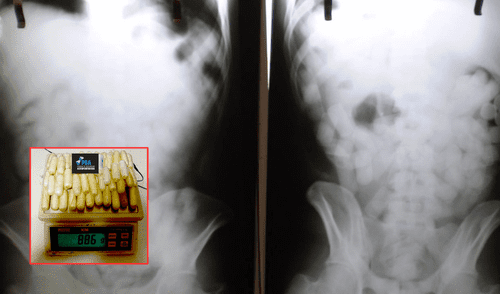

La Policía de Seguridad Aeroportuaria (PSA) abordó a Morales en Ezeiza, donde, a pesar de tener su documentación en regla, no pudo justificar su paso por Buenos Aires. La tomografía realizada confirmó la presencia de cuerpos extraños en su abdomen, lo que llevó a su traslado al Hospital de Ezeiza bajo custodia policial. Durante su internamiento, expulsó 90 cápsulas de cocaína, cada una de las cuales fue entregada a las autoridades para su análisis.

El informe médico indicó que Morales tuvo suerte, ya que una ruptura de las cápsulas podría haber resultado fatal. El juez Marcelo Aguinsky, encargado del caso, dictó prisión preventiva y un embargo de 48 millones de pesos argentinos, lo que equivale aproximadamente a S/1.056.000, y enfatizó la gravedad del delito y el método utilizado por el joven, al que describió como una “bomba viviente”.